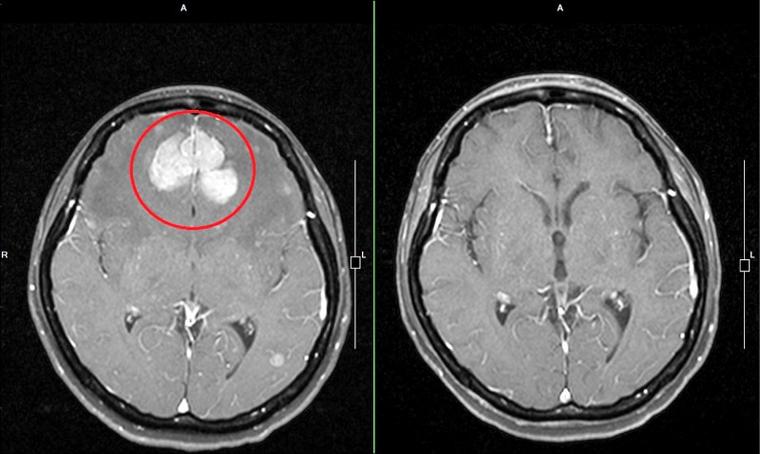

- 头颅MRI + DWI序列:这是诊断早期脑梗的“金标准”,可以清晰地显示缺血坏死的脑组织。

- CTA/MRA(血管成像):评估脑血管是否有明显的狭窄、闭塞或血栓形成。